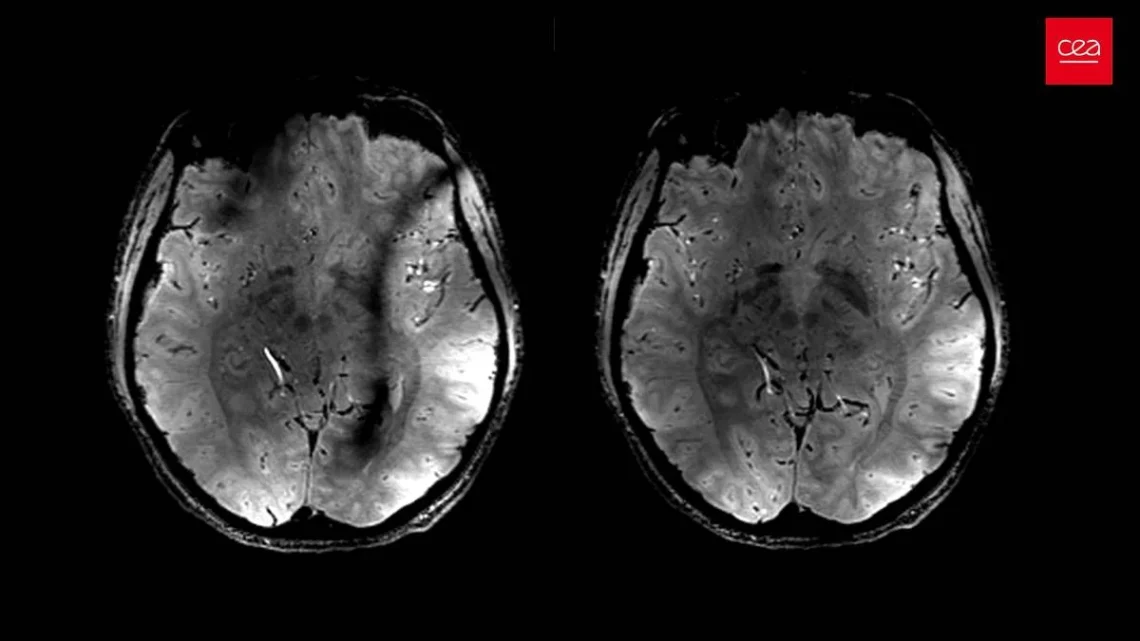

ecorrendo a um modelo de IA de aprendizagem profunda para analisar TACs ao tórax de rotina, os cientistas conseguem identificar um marcador biológico inédito de stress crónico.